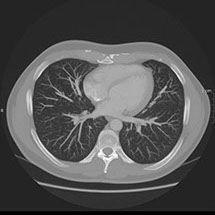

Le scanner comporte un lit d'examen, sur lequel le patient est allongé, qui va se déplacer lentement pendant l’examen et un anneau qui va tourner autour du patient en émettant des rayons X (il contient le tube à rayons X et les récepteurs). Les rayons X vont traverser la région à étudier et permettre d’obtenir des images en coupe de la zone à étudier. Des traitements de numérisation informatique permettront d'obtenir  des images 2D ou 3D dans différents plans et volumes.

• Les pathologies thoraciques (infection, tumeurs …).